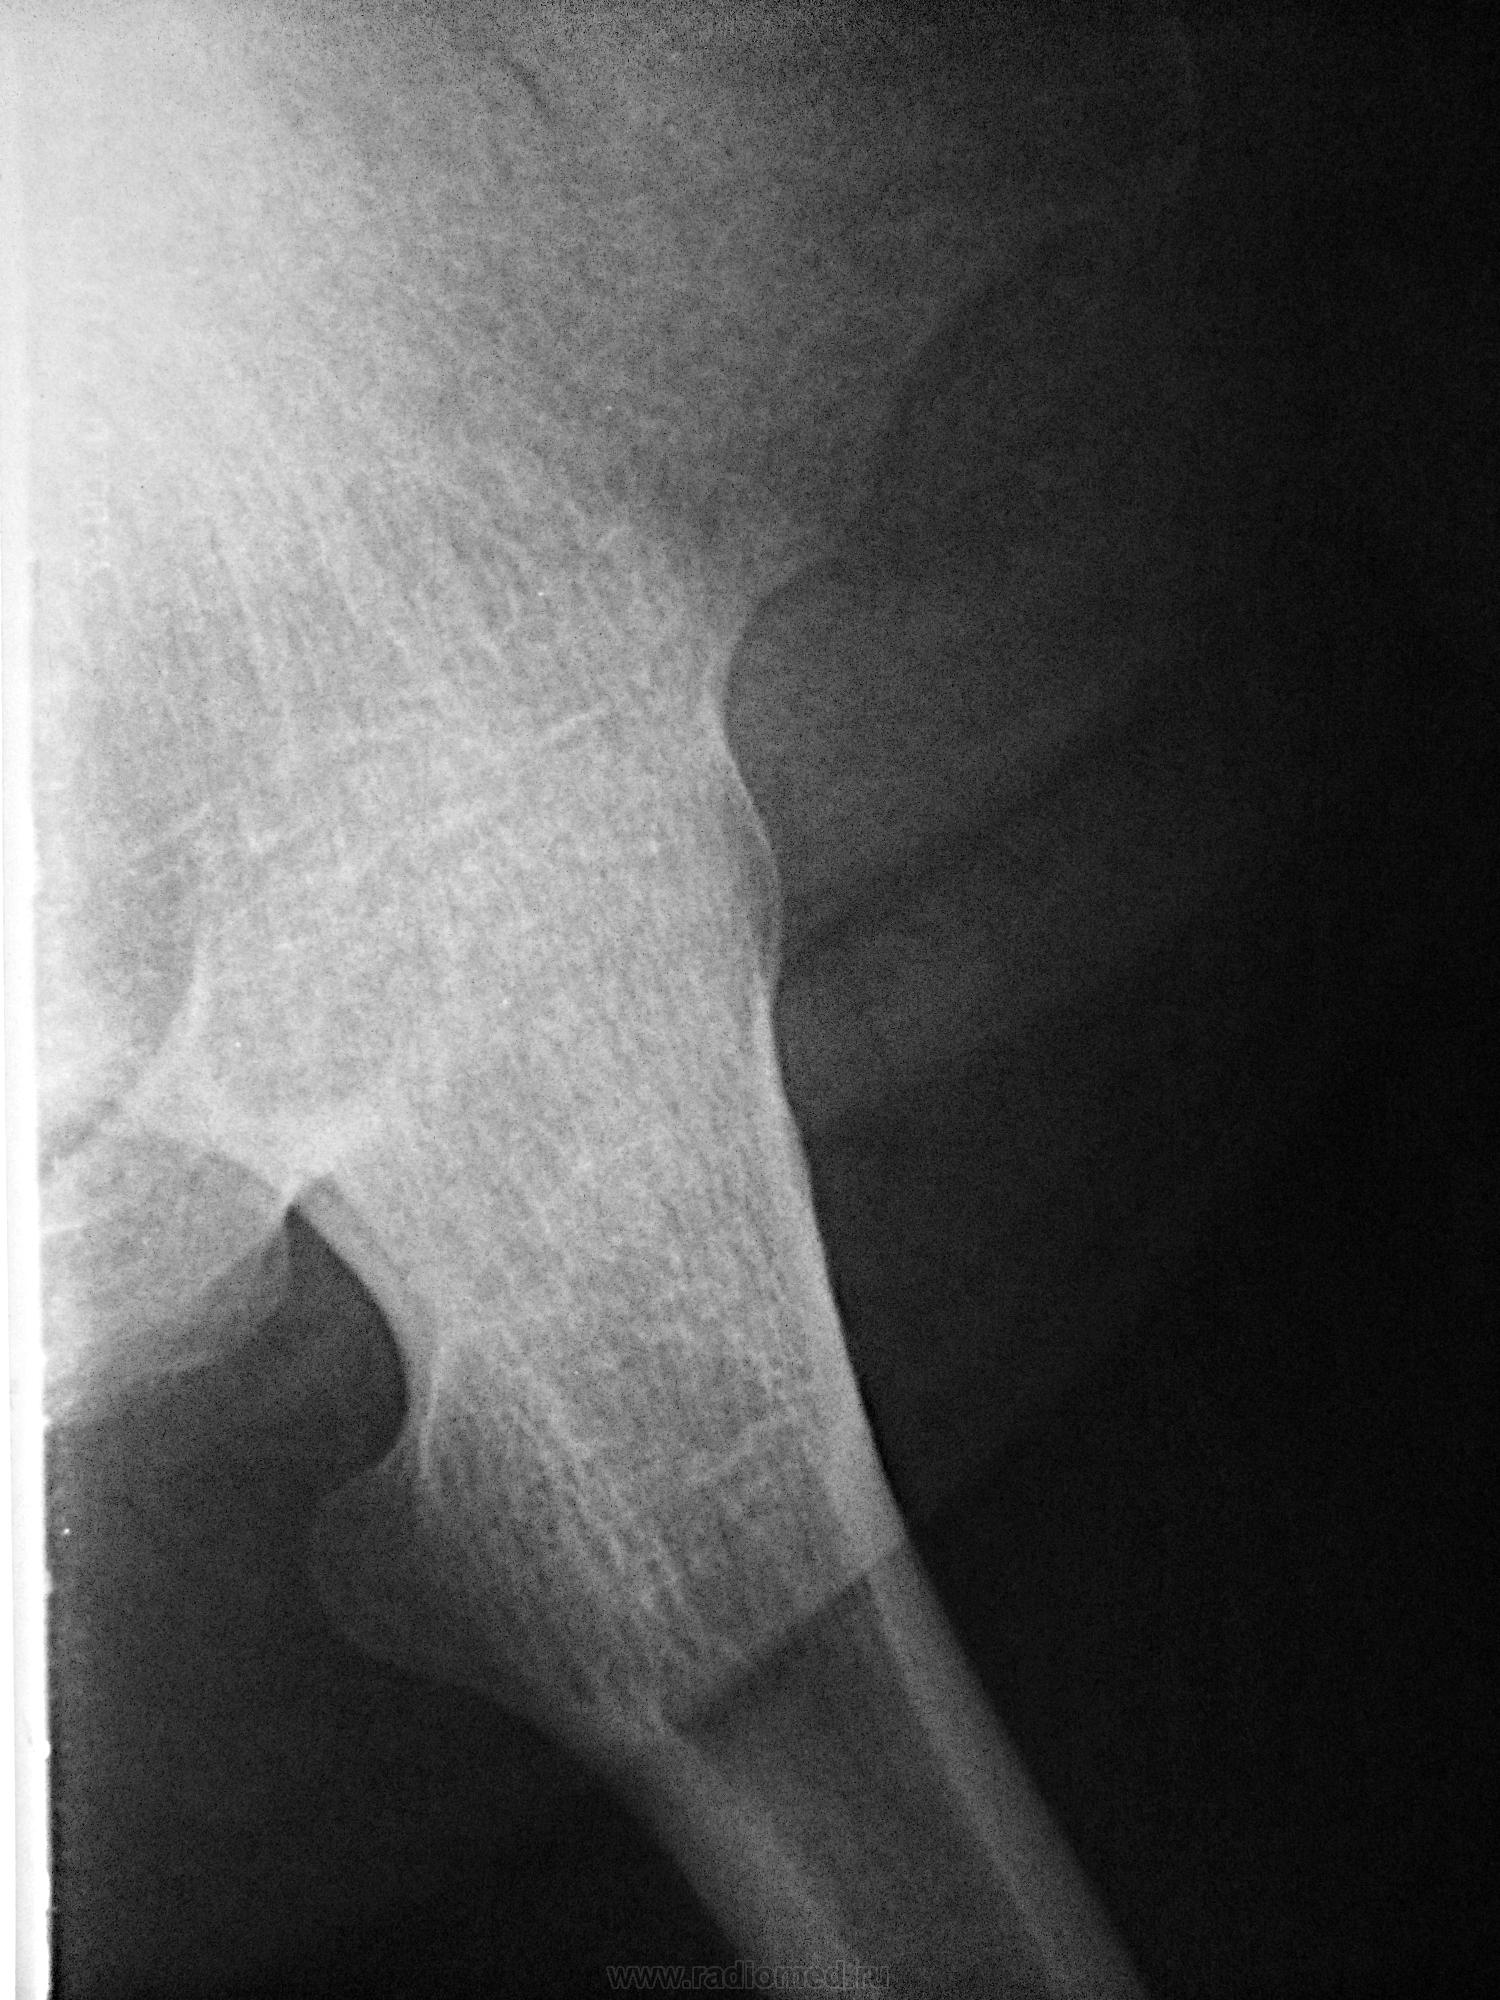

Рентгеновские снимки анкилоза суставов: Как это выглядит